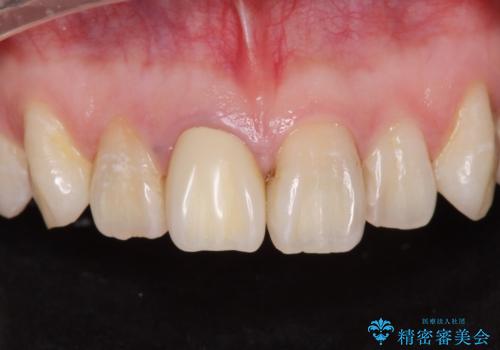

[歯と歯の間の虫歯] ジルコニアクラウン

- メンテナンスの患者様です。レントゲンで歯と歯の間の虫歯が発見されたため治療を行うことになりました。

歯質全体が粗造になっており、インレー治療だと虫歯になる可能性があるので被せ物での治療となりました。

適合が良い被せ物が入りました。

毎日フロスや歯間ブラシを行うことで歯と歯の間が虫歯になるリスクが低くなります。